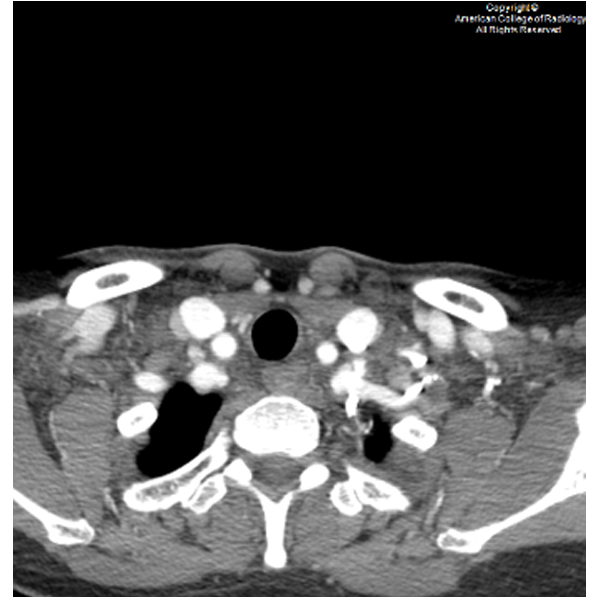

A 39-year-old female presents to the emergency room with lower abdominal pain for the past 2 weeks.#ACRCaseinPoint

https://t.co/Kf53OLIc16